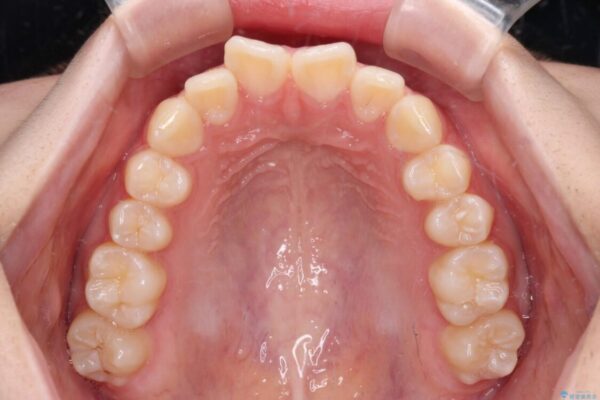

治療後

• インビザラインは使える自信がない ワイヤー装置にて矯正治療 治療後画像